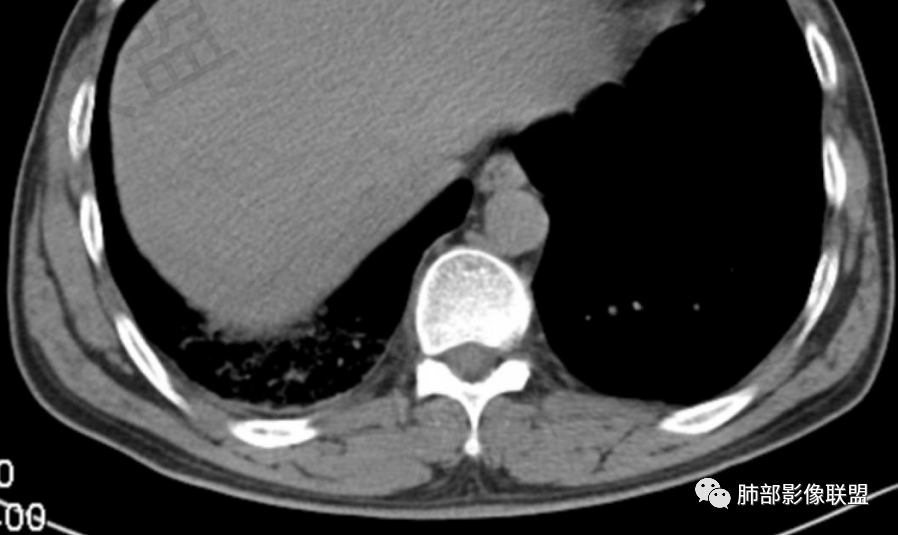

肺动脉栓塞

肺动脉栓塞(简称PE)为内源性或外源性栓子堵塞肺动脉或其分支引起肺循环障碍的临床和病理生理综合征,是常见的且具有潜在致死性的心血管疾病,90%为肺动脉血栓栓塞。

CT肺动脉成像(CTPA)以其高度的敏感度和特异度,已经作为临床上诊断急性肺栓塞的首选方法。

急性肺栓塞患者CTPA上胸部继发改变包括肺动脉干增粗、右心增大、肺梗死、马赛克征、Westermark征、心包积液、胸腔积液、肺不张/肺膨胀不良等。

肺动脉高压的标准以肺动脉干直径大于3 cm或肺动脉干直径大于同层面升主动脉直径。右心增大的标准以横断位四腔心层面右心室内径与左心室内径比值大于1,或出现室间隔变直或凹陷等征象。

急性肺栓塞发生后,因肺动脉血流阻断而引起供血动脉远端肺组织的坏死称为肺梗死。肺动脉分支一旦血流阻断,远端毛细血管网则因管壁缺氧而通透性增高,液体及红细胞随之渗出,肺泡腔内渗出物增加,必然会影响气体交换,随后肺梗死发生。既往有研究表明,肺外周楔形阴影可以认为是肺梗死的征象,是唯一与肺栓塞显著相关的肺实性异常,该征象在肺栓塞患者中的发生率为25%。

Westermark征是指当肺叶或肺段动脉栓塞时,相应范围的肺纹理减少或消失,透亮度增高。